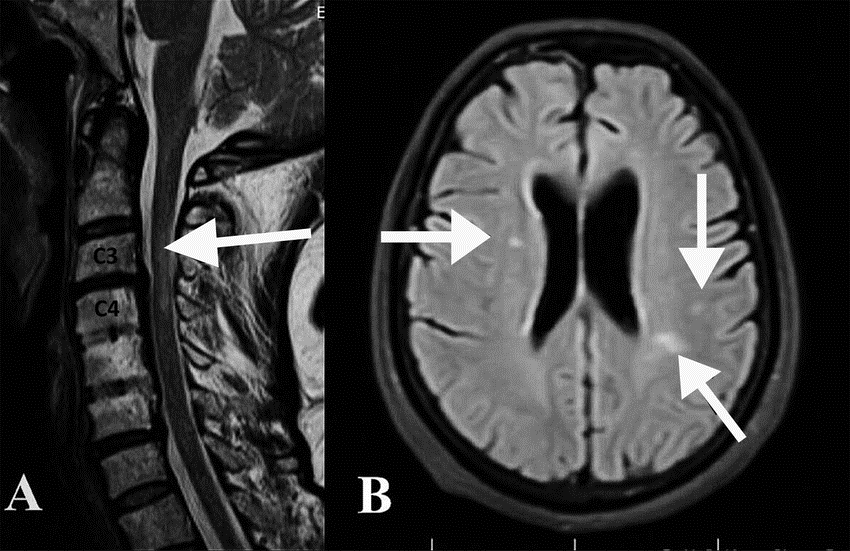

• magnetna rezonanca mozga i kralježnične moždine

MAGNETNA REZONANCA (MRI)

Magnetna rezonanca najvažnija je neuroradiološka metoda u dijagnostici multiple skleroze.

Na MRI snimkama mogu se uočiti demijelinizacijski plakovi u bijeloj tvari mozga i kralježnične moždine.

Važno je razlikovati nalaz multiple skleroze od tzv. klinički izoliranog sindroma, koji predstavlja samo jednu kliničku manifestaciju s jednom izoliranom demijelinizacijskom lezijom.

MRI je vrlo osjetljiva metoda koja također omogućuje isključivanje drugih bolesti koje mogu oponašati simptome multiple skleroze.